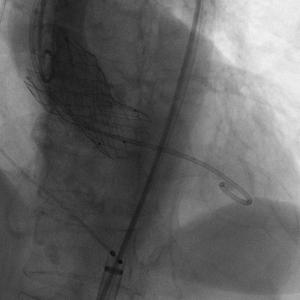

患者插管后已可以耐受造影剂,常规左侧作为辅入路进行操作,翻山造影后进行穿刺等操作,患者辅入路植入猪尾造影,根据造影调整体位使无窦,右窦,左窦分离,右窦居中,三个窦保持在同一平面,之后常规跨瓣进行后续操作。

Numed18球囊扩张